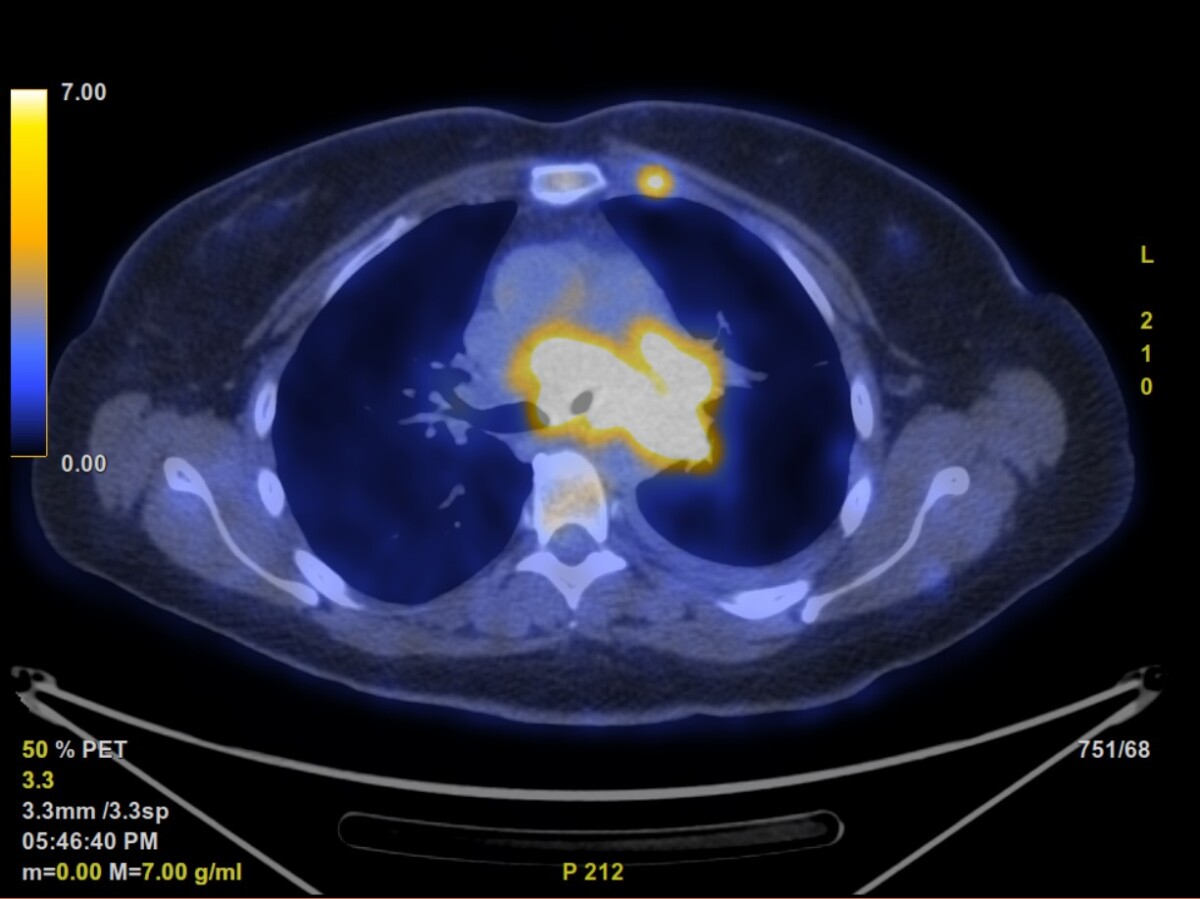

The culprit

This is the scan from mid October that identified my primary lung tumor. The smaller yellow spots you see around (excluding the mass in the middle) are metastasis that have spread to my bones.